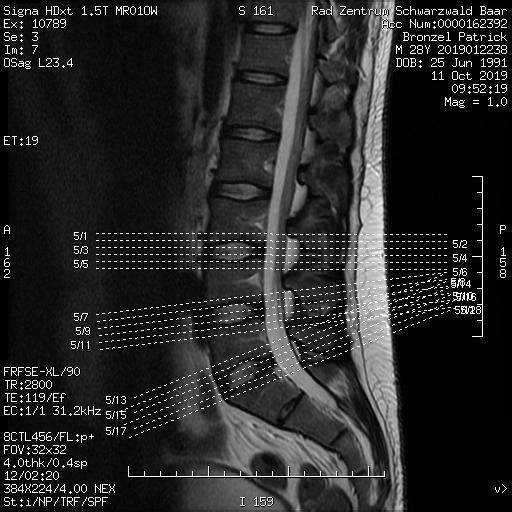

Ein Überbrückungsrahmen entlastet die Lendenwirbelsäule, indem er eine Lastenumverteilung innerhalb der gesamten Wirbelsäule bewirkt.Die Implantation einer Bandscheibenprothese erfolgt im Bereich der Lendenwirbelsäule durch den Bauch und im Bereich der Halswirbelsäule von ventral. Die Arthrose, d. Typ 2) Einsatz von Pedikelschrauben Bei einer starken Veränderung oder Abnutzung (Degeneration) eines Wirbelsäulenabschnitts können spezielle Schrauben eingesetzt werden, mit denen das .Die Lendenwirbelsäule ist ein Teil der Wirbelsäule des Menschen und besteht aus 5 einzelnen Knochen, den Lendenwirbeln (Vertebrae lumbales), die von kranial nach kaudal als LW1 – LW5 durchnumeriert werden.Der Rücken verbleibt dabei auf dem Boden. Außerdem gibt es Rückenorthesen zur Korrektur von Fehlhaltungen und Fehlstellungen.

Ein Lendenkissen (bzw. Des Weiteren wird dadurch die Blutzirkulation angeregt.Deine Muskeln werden aktiviert und gestärkt, wodurch sie Deinen Gelenken besseren Halt geben können diese entlasten. Auch zur Vorbeugung gegen einen Bandscheibenvorfall lohnt es sich, das volle Bewegungsspektrum deiner Wirbelsäule auszuschöpfen.Die Lendenwirbelsäule ist der unterste Abschnitt unserer Wirbelsäule. Es ist der Teil der Wirbelsäule, der uns am häufigsten Probleme bereitet – wir alle kennen das als Kreuzschmerzen, fachlich auch LWS-Syndrom oder Lumbalgie genannt.

Ausreichend Bewegung. Wenn du in Rückenlage schläfst, solltest du ein Kissen unter deine Knie legen, um die . Schon ganz einfache Dehnübungen können dir dabei helfen die Lendenwirbelsäule zu entspannen. Durch die Anstrengungen beim Sport intensiviert sich Deine Atmung, was zu einer besseren Durchblutung Deiner Muskulatur führt. Muskelverspannungen im unteren Rücken.Übergewicht zu vermeiden, entlastet ebenfalls die Wirbelsäule. Zudem verbessert man mit Inlineskating .Die Lendenwirbelsäule ist der untere Teil deines Rückens, und sie hat eine wichtige Aufgabe: Sie stützt den Großteil deines Oberkörpers, wenn du stehst oder sitzt. Lesen Sie alles Wichtige über die Wirbelsäule: Aufbau, Funktion sowie wichtige Erkrankungen und Verletzungen .

Bandscheibenvorfall: Symptome, Diagnose, Therapie

Die Lendenwirbelsäule: Aufbau & Bedeutung